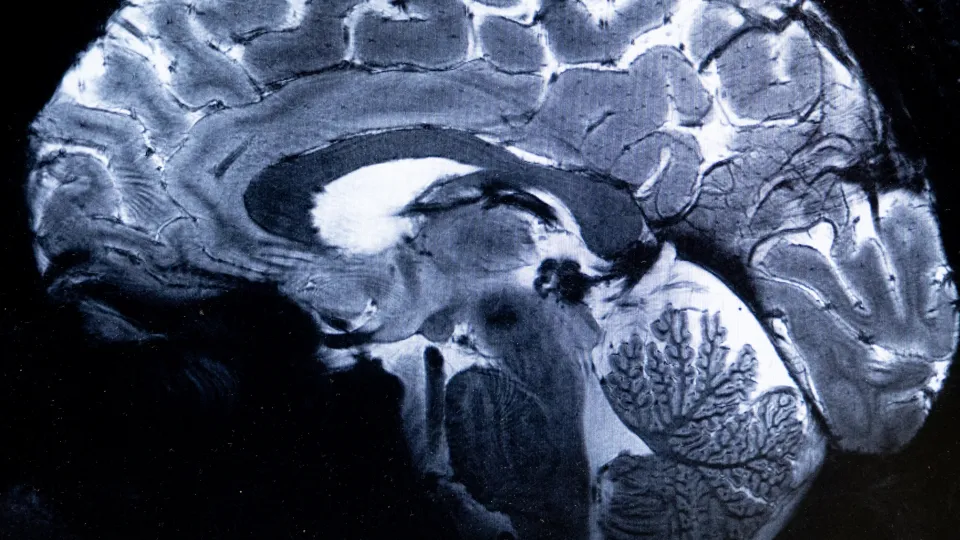

實驗進一步證實,相較於獨自穿行,附著在囊泡上的荷爾蒙更容易穿透保護嚴密的人體「血腦屏障」。儘管科學家仍需研究荷爾蒙到達大腦後的具體行為,但此發現對心理健康、代謝性疾病、發炎反應及止痛治療,甚至是新藥的標靶輸送都有深遠意義。對內華達居民而言,這項研究給了大家更多「動起來」的理由:每一次汗水,都在以科學家才剛開始理解的方式,重塑大腦的化學環境。